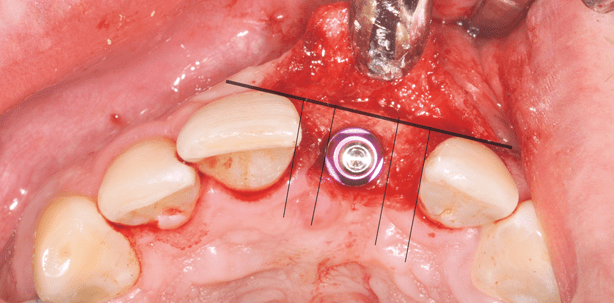

Die Implantation erfolgte vier Monate nach dem Knochenaufbau. Nach der Lokalanästhesie wurde ein vestibulärer Lappen präpariert, der Kieferknochen dargestellt und die beiden Osteosyntheseschrauben entfernt (Abb. 17). Die Pilotbohrung wurde mithilfe der Implantatschablone durch die zwei teilige CAMLOG-Hülse für CT-Planung (2,2 mm Durchmesser) durchgeführt (Abb. 18). Alle weiteren Bohrerschritte für die Aufbereitung des Implantat lagers für das Implantat (CAMLOG® SCREW-LINE), Länge 13 mm und Durchmesser 4,3 mm führten wir ohne Schablone durch. Die Platzierung des Implantats erfolgte dreidimensional nach den Kriterien des anatomischen Fensters nach Gomez und der Berücksichtigung der biologischen Umbauprozesse, die mit einer Implantatversorgung einhergehen. Im vorliegenden Patientenfall kam die Implantatschulter 1–2 mm unterhalb der Schmelz-Zement-Grenze der Nachbarzähne zu liegen. In oro/vestibulärer Ausrichtung wurde die Implantatschulter ca. zwei Millimeter palatinal des Zahnbogens platziert. Die apikale Platzierung erleichtert es, die Unterschiede zwischen dem anatomischen Kronendurchtrittsprofil und dem Implantatdurchmesser auszugleichen. Der mesio/distale Abstand von Implantataußenkante zum Nachbarzahn sollte zirka zwei Millimeter betragen (Abb. 19 und 20). Das Implantat wurde mit der Abdeckschraube verschlossen, das Weichgewebe vernäht und zur Kontrolle eine Röntgenaufnahme gemacht (Abb. 21).